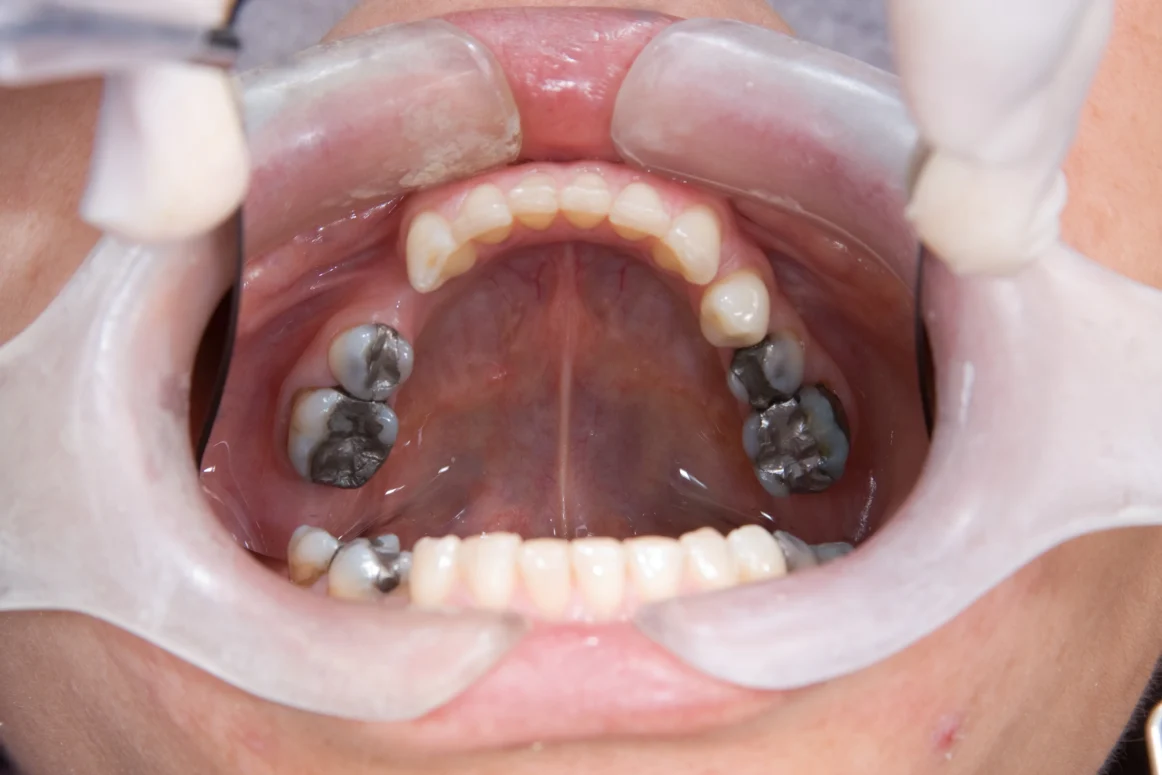

Amalgam fillings, the classic “silver” or “mercury” fillings, tell a clear story every time you open your mouth. They’ve done their job for years: strong, durable, and widely used. But they also come with two big drawbacks for today’s patients; they contain mercury (a toxic metal) and leave a dark, metallic shadow in an era where bright, natural smiles are the norm.

With more people choosing cosmetic treatments such as the Hollywood Smile in Turkey, many patients now feel their older black fillings are not in harmony with the rest of their teeth and can make their smile look older in photos and everyday life. That’s why modern cosmetic dentistry is shifting away from placing new amalgam fillings and towards safely removing old ones and replacing them with tooth-coloured, mercury-free restorations that blend seamlessly with the natural smile.